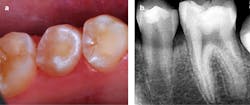

- There was no clinical evidence of the caries lesion from the occlusal aspect (figure 2a).

- Access to the lesion was gained with a water-cooled high-speed diamond cylinder bur.

- The carious tooth structure was debrided using slow-speed round burs (figure 2b), and cavity outline was completed with a slow-speed diamond cylinder and inverted cone carbide burs.

- The premolars were photographed four months postoperatively (figure 6a), and a periapical radiograph of the second premolar was recorded at that time—August 2023 (figure 6b).